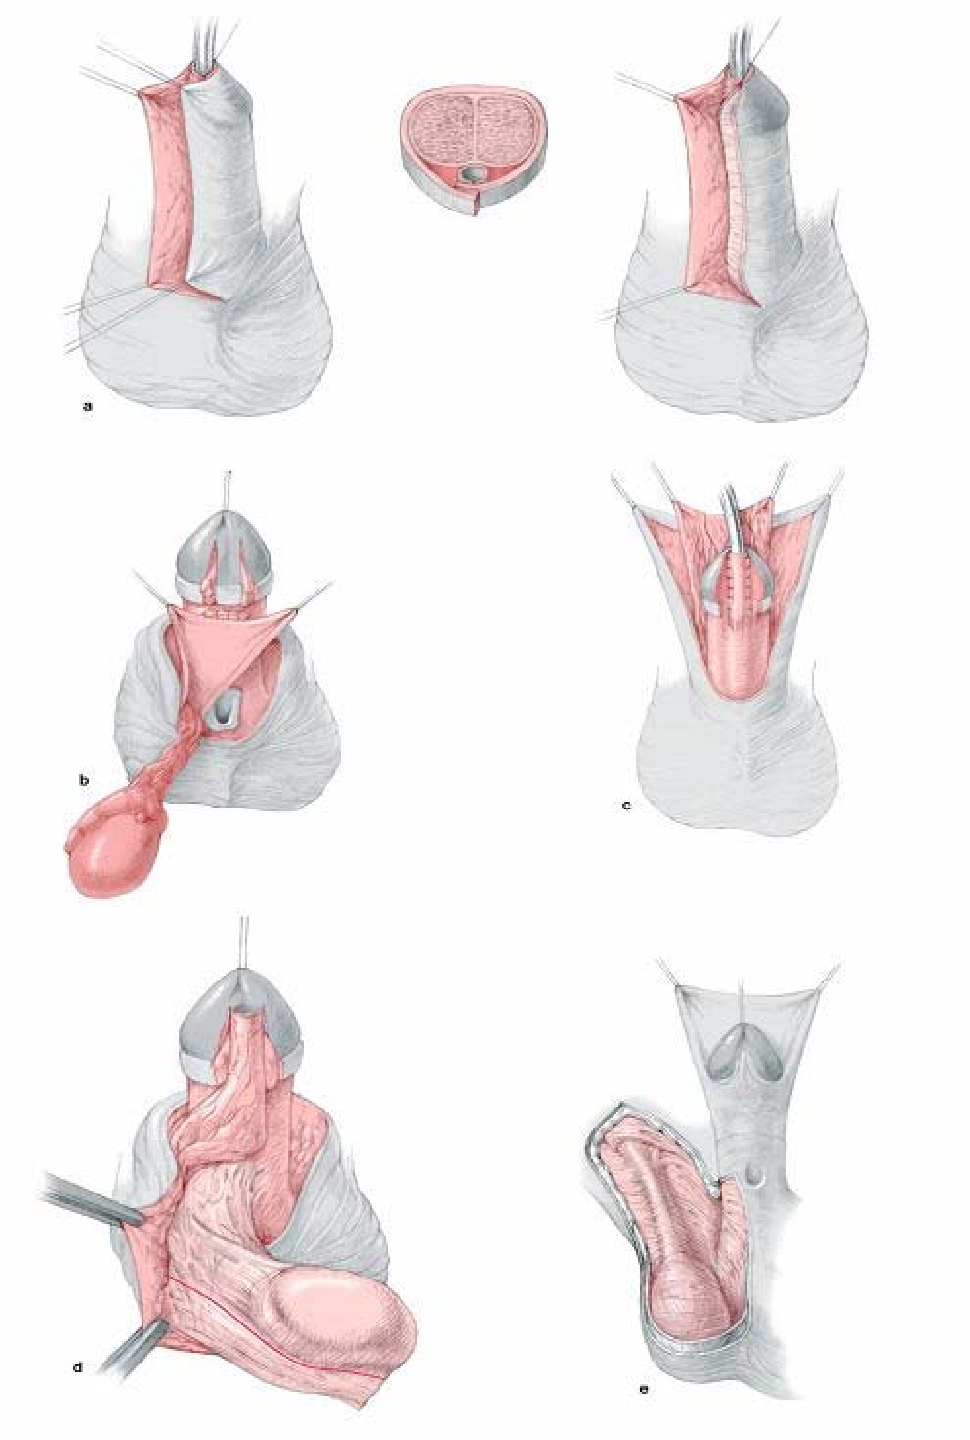

Лабиопластика

Лабиопластика, также известная как лабиопластика, заключается в хирургической модификации больших или малых половых губ, но чаще всего это уменьшение размера малых половых губ (рис.) и является одной из наиболее часто выполняемых процедур FCGS. Часто цель состоит в том, чтобы сохранить контур губ и сохранить цвет губных краев. Различные хирургические методы включают криволинейную резекцию, резекцию V-образным клином, резекцию нижнего клина и реконструкцию верхнего лоскута на ножке, Z-пластику и другие менее используемые методы.

Лабиопластика

Лабиопластика, также известная как лабиопластика, заключается в хирургической модификации больших или малых половых губ, но чаще всего это уменьшение размера малых половых губ (рис.) и является одной из наиболее часто выполняемых процедур FCGS. Часто цель состоит в том, чтобы сохранить контур губ и сохранить цвет губных краев. Различные хирургические методы включают криволинейную резекцию, резекцию V-образным клином, резекцию нижнего клина и реконструкцию верхнего лоскута на ножке, Z-пластику и другие менее используемые методы.